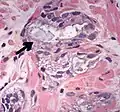

Intraductal carcinoma of the prostate with very patchy basal cells identified by immunohistochemistry. At least some of the glands lacking basal cell immunoreactivity represent intraductal rather than invasive carcinoma (a haematoxylin and eosin, b CK 5/6)[20]